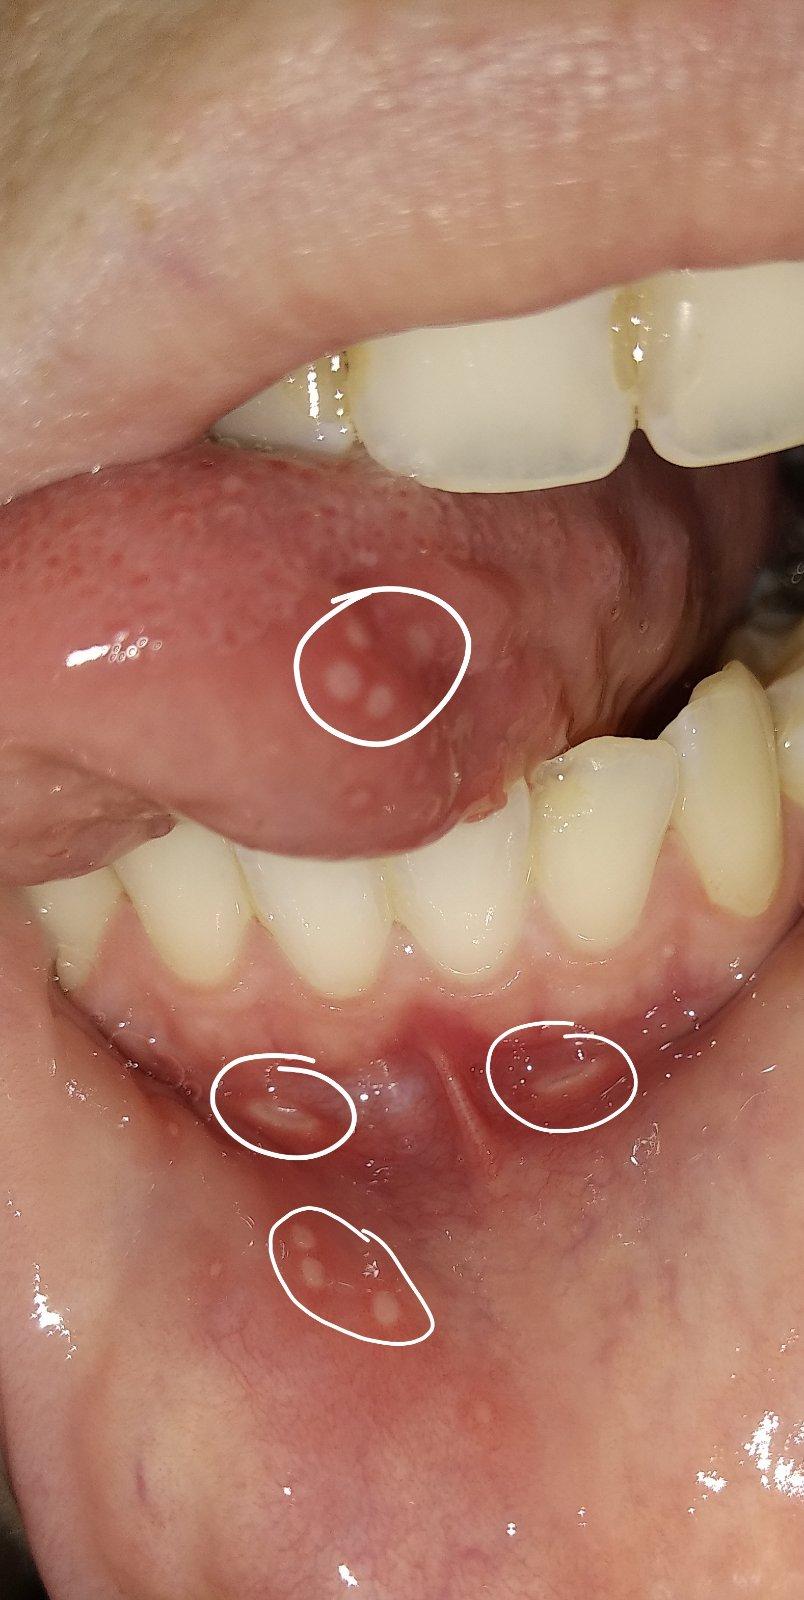

Baby, ktoré máte problém s častými aftami, čo vám zaberá?... skúšala som propolis, tea tree, taký gélik Lips, homeopatiu borax, ústnu vodu, pálenku, pastu meridol a nič nezaberá absolútne... najhoršie na tom je že drobec začal mať rovnaký problém a teraz ich máme každý 1-2 mesiace.. snažím sa aby nebol v kontakte s mojimi slinami ale poznáte to..neustrážim sa, dám mu napiť z môjho pohára, dám mu do úst moju lyžicu a tak... tentokrát nakazil on mňa, mal skôr a mne sa včera vyhodili, 4 na jazyku, 2 pri spodnej pere...aaach je to na nervy toto štípe to jak ďábel...tu bude asi nejaký vnútorný problém ale nerada by som to riešila cez lekárov a chémiu...drobec mi odmieta jesť, stále si pchá pršteky do pusy ale nie zo zúbkov, keď sú zúbky kuše si do nich, teraz len prikladá...ach viem ako sa musí cítiť ☹

A mne nezabera nic.a to ich mam 2_3krat za mesiac 😢 aj teraz mam uz par dni.chodim na doplnenie zelezia infúzie.beriem aj B12 inekcie,bekomplex forte,D,acidum folikum,inunologia dopadla bez nalezu,alergia sa nepotvrdila,no aj tak od januara sa to rapidne zhorsilo a vobec neviem z coho.uz som mala aj fest zapal dasien z toho.